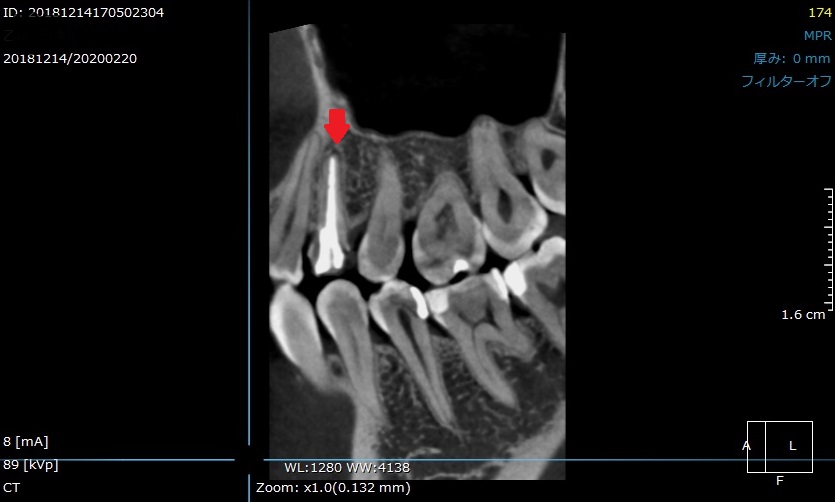

「歯を抜かないといけない」と言われたが、当院で抜かずに終えました。